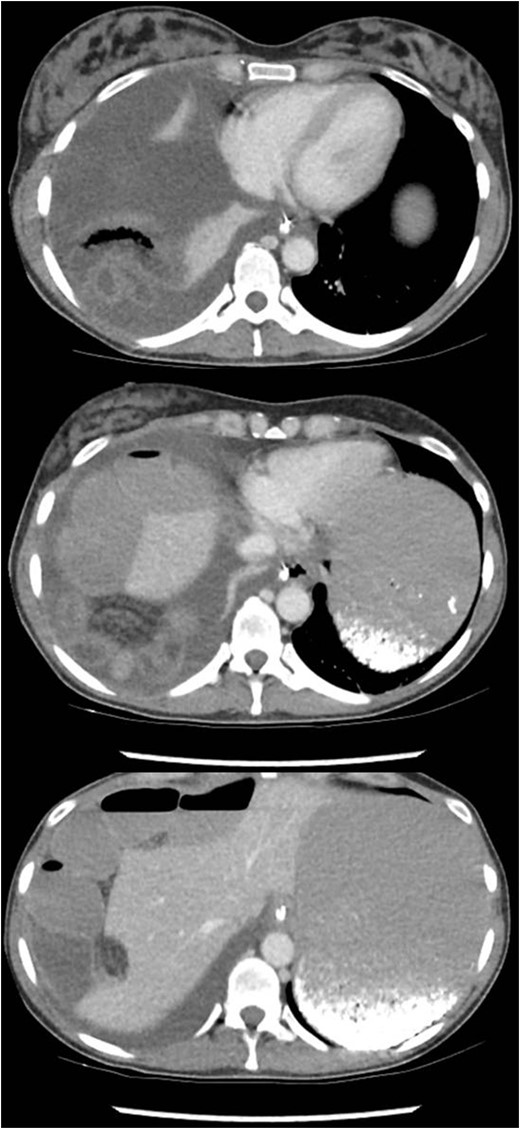

A healthy 41-year-old female, 38-week pregnant, presented with irretractable abdominal pain and vomiting. There was no previous similar history or abdominal surgery. She associated the onset of symptoms with a low energy fall on to her buttocks. There was no improvement despite hastening her elective caesarean section. Thereafter, she was treated as a post-operative ileus (Fig. 1). On multiple examinations, she remained afebrile and haemodynamically stable. The abdomen was distended, with generalized mild tenderness. Bowel sounds were audible. Blood tests were unremarkable. Failure to progress prompted further evaluation with CT. This revealed a small bowel obstruction secondary to a right-sided diaphragmatic hernia (Fig. 2). After resuscitation, she proceeded to laparoscopy.